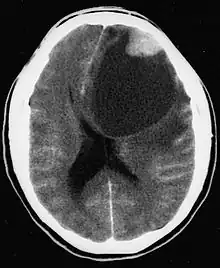

CT scan of a brain with pleomorphic xanthoastrocytoma. The classic radiographic appearance is one of a superficially situated tumor, here a mural nodule, associated with an underlying cyst. |